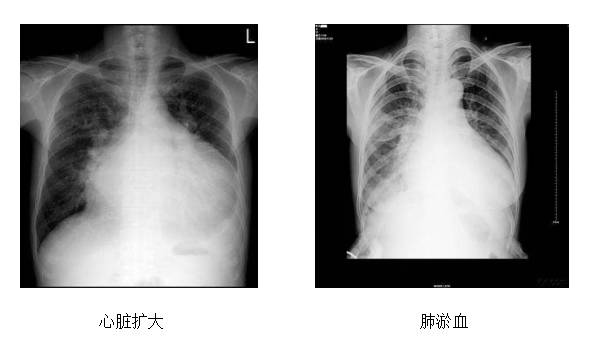

容量评估二:胸部X线及超声心动图

◆胸部X线

▷心脏扩大

▷肺淤血

▷肺水肿

▷胸水